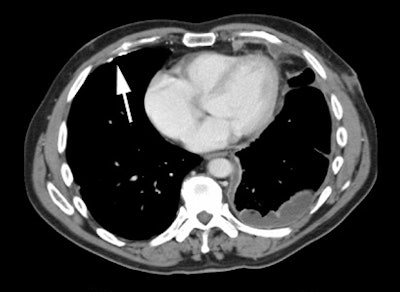

Hepatocellular carcinoma: The patient shown below also has a large hepatocellular carcinoma. The FDG PET exam (right) demonstrated no uptake of tracer within the lesion (black arrows). |

|